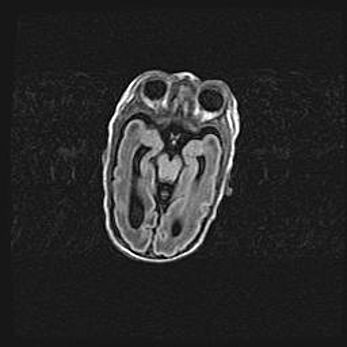

Сообщающаяся гидроцефалия. Кистозная энцефаломаляция головного мозга.

Возраст: 3 месяца 4 дня

Вес: 3100 г

Пол: женский

Окружность головы: 34 см

Срок гестации: 31 неделя

Кистозная энцефаломаляция головного мозга - одна из форм поражения головного мозга в детском возрасте. Характеризуется возникновением множественных и распространённых кист в коре, белом веществе и подкорковых образованиях головного мозга у плодов, новорождённых и детей раннего возраста. Развитие кистозной энцефаломаляции связано с внутриутробной асфиксией и гипотонией, родовой травмой, тромбозом синусов, пороками развития сосудов, инфекциями, сепсисом и другими причинами. Наиболее значимые инфекционные агенты: вирусы простого герпеса, цитомегалии, краснухи, токсоплазмы, энтеробактерии, золотистый стафилококк и другие.